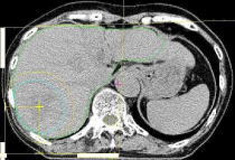

位置決めCTの画像を基本として、腫瘍の大きさや進展範囲を判断し、適切な粒子線の照射範囲や方向、線量の処方を行います。

【1】CT検査だけでは腫瘍の進展範囲がわかりにくいことがあるため、必要に応じて同じ場所のMRI画像とCT画像の重ね合わせ(フュージョン)を行います。

【2】画像をもとに腫瘍の範囲を指定し、腫瘍の形状を治療計画装置上で定義します。呼吸や体の動きによる誤差も考慮して適切な粒子線の照射野の形状を決定します。また、副作用の可能性のある臓器の指定も行います。

【3】粒子線を照射する方向やエネルギー、深さを決定します。この時に治療計画装置上で試行錯誤を繰り返し、もっとも副作用を少なくすることのできる、効果的な治療法を選びます。

【4】最後に計画情報の保存・出力を行います。

位置決めCT元画像

腫瘍形状の指定

2次元線量分布図

3次元線量分布図

治療計画装置で作られた画像